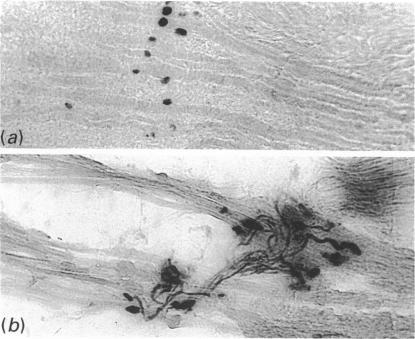

In previous studies of middle ear muscles, the classification of fibre types by histochemical methods was particularly difficult in the bovine and porcine tensor tympani muscle, suggesting the presence of immature fibres. We therefore reexamined the tensor tympani from pigs and cattle of various ages immunohistochemically, using a panel of antimyosin antibodies, including one (anti-NE) specific for neonatal and embryonic myosins. Fibres positive to anti-NE were found in tensor tympani in both species in all ages examined; only a few of these fibres reacted exclusively with this antibody; some also contained slow myosin and the majority also contained adult fast (type IIA) myosin. Furthermore, although the remaining fibres included some of the classical types I and IIA, the majority of them showed a mismatch between their histochemical and immunohistochemical profiles. The morphological appearance of the muscle, the widespread presence of neonatal myosin (often together with another myosin in the same fibre) and the persistence of this composition from birth to adulthood, could be explained by an incomplete development of the muscle fibres, resulting in a 'muscle' much better suited to the role of a ligament.